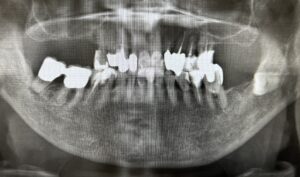

そもそもインプラントは失った歯を自分の歯の代わりとして人工の歯根を顎の骨に埋め込み、その上に人工の歯を装着して噛み合わせを回復する治療法です。

上の歯が難しいとされている大きな要因は下記の通りです。

【歯根部の硬さの問題】

・顎の骨は、皮質骨と海綿骨で構成されている

・上顎は下顎よりも海綿骨の比率が高い

・歯根部を埋入するための硬さがやや不足しているケースが多い

【骨密度の問題】

・上顎は下顎に比べて骨密度が低い

・顎の骨に埋入した歯根部の結合に時間がかかる

・上記の理由から上の歯はインプラント治療が難しい

【副鼻腔の問題】

・顎の骨が薄いケース

・切歯管内の組織を巻き込まないように注意しなければならない

・インプラント周囲炎を起こすと上顎洞炎の原因になる